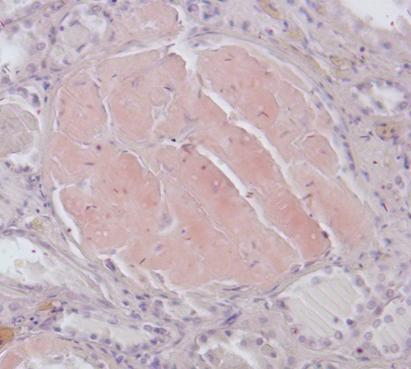

Гистологическое исследование. Сердце – кардиомиоциты гипертрофированы, диффузный кардиосклероз. При окраске на амилоид в строме и стенке сосудов отложение амилоидных масс (рис. 1). Селезенка – красная пульпа полностью замещена однородными массами, дающими положительную окраску на амилоид (рис. 2).

Рис. 2. Амилоид в красной пульпе селезёнки. Окраска конго красный, ×200

Почки – резкое уменьшение числа клубочков, отдельные полностью замещены однородной массой, дающей положительную реакцию на амилоид (рис. 3). В стенке сосудов также видны отложения амилоида (рис. 4).

Рис. 3. Почечный клубочек замещен амилоидными массами. Окраска конго красный, ×400